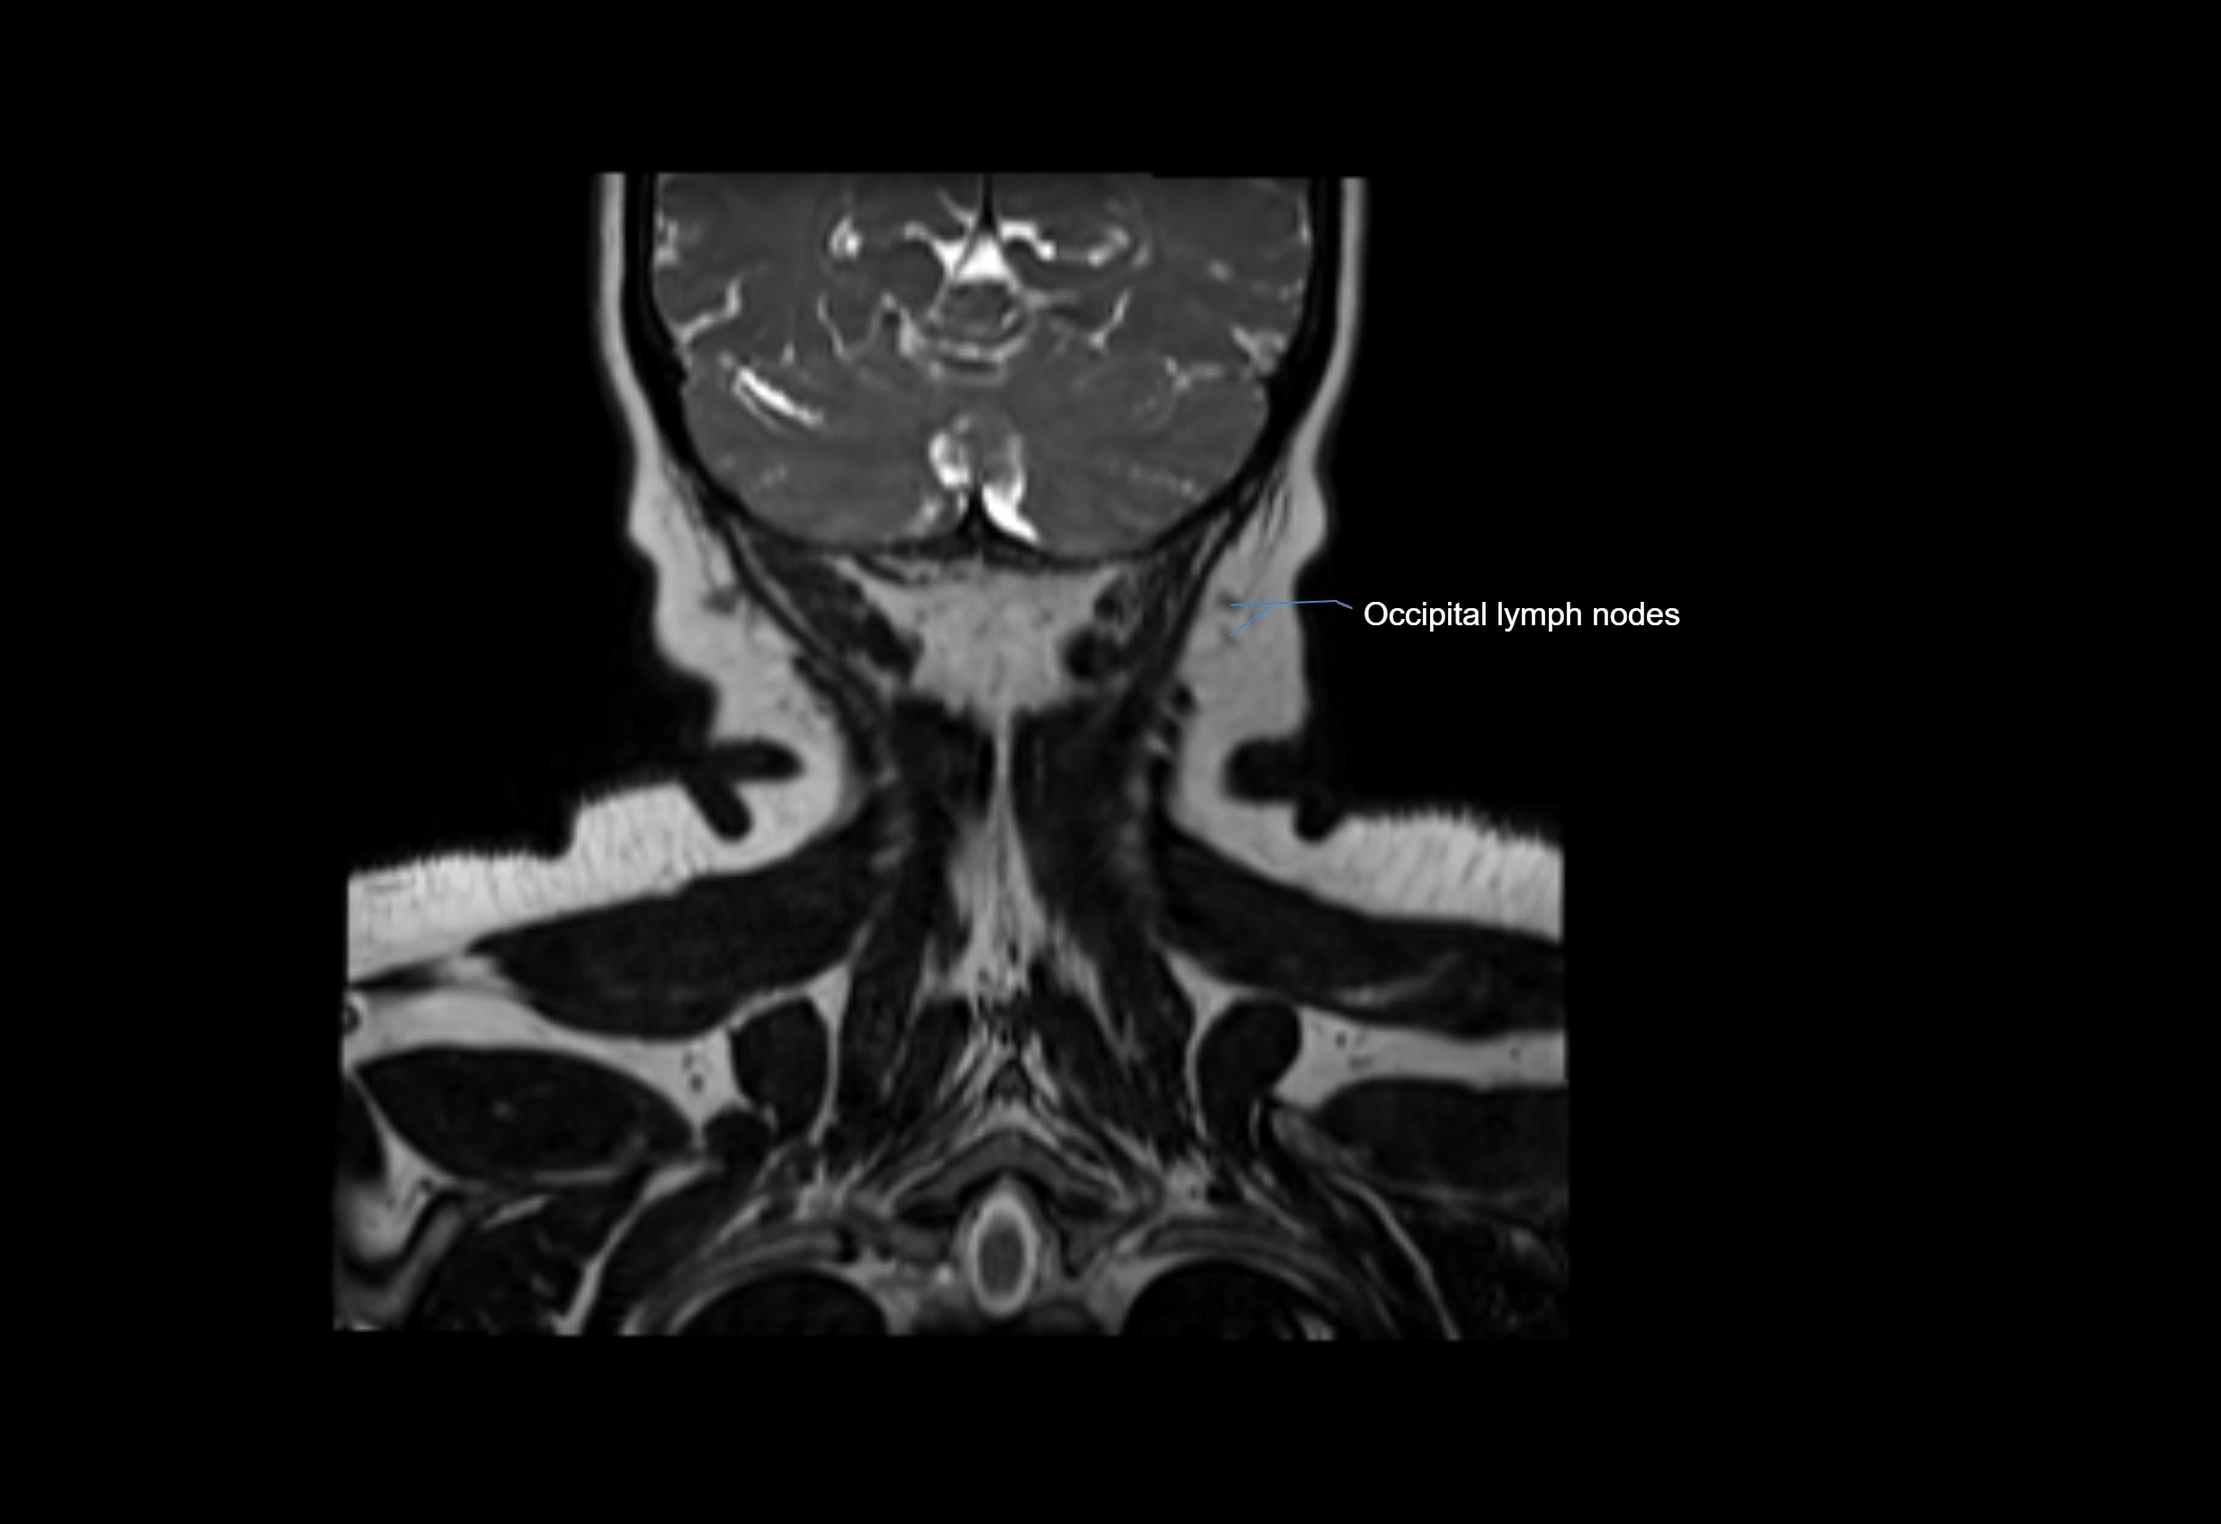

Location

• Found along primary lymph node chains, including preauricular, submandibular, parotid, and occipital regions

• Embedded in subcutaneous fat or superficial fascia, often lateral or posterior to primary nodes

MRI Appearance

T1-weighted images:

• Normal accessory nodes appear as small, oval hypointense to intermediate signal structures within subcutaneous fat

• Surrounded by hyperintense fat, enhancing contrast for visualization

• Pathological nodes may appear enlarged or rounded, sometimes with cortical thickening

T2-weighted images:

• Nodes show intermediate signal, with surrounding fat bright

• Useful for detecting edema, inflammation, or infiltration

• Fatty hilum may appear slightly hyperintense relative to cortex

MRI images

image